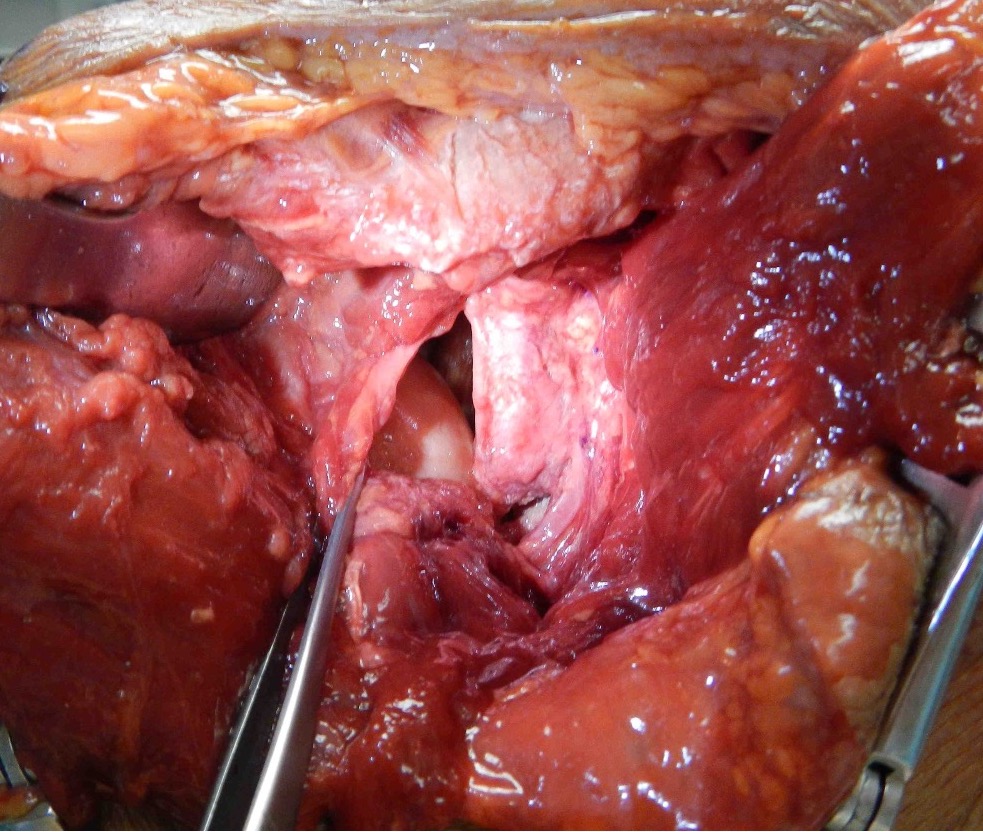

Beach chair or lateral position

- posterior approach / L shaped incision

- elevate or detach deltoid from scapular spine

- detach infraspinatus

- iliac crest or distal tibial allograft

Identify and elevate deltoid / detach from scapular spine / identify infraspinatus

Identify interval between infraspinatus and teres minor, detach and reflect infraspinatus to expose posterior capsule and glenoid